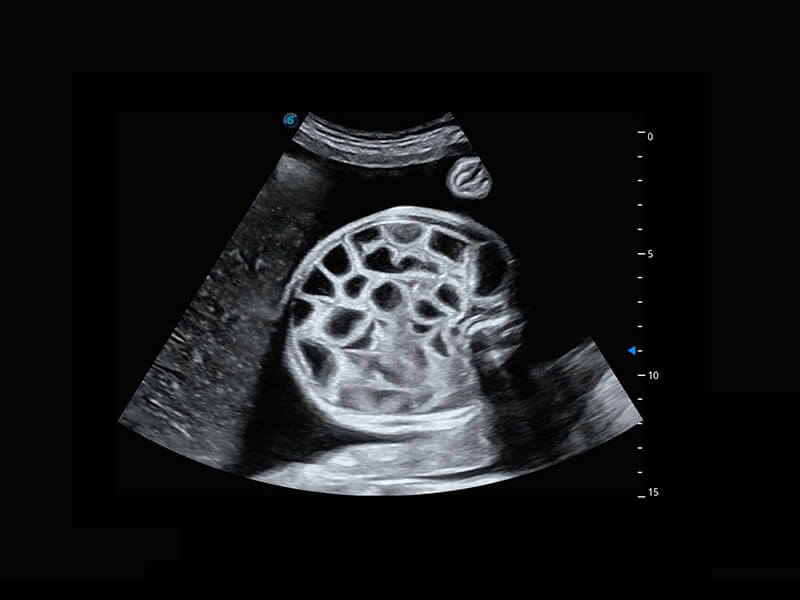

胎心筛查

P60搭载一系列胎儿心脏成像技术,实现精细的胎儿心脏评估。

• 四腔切面

• 胎心容积成像